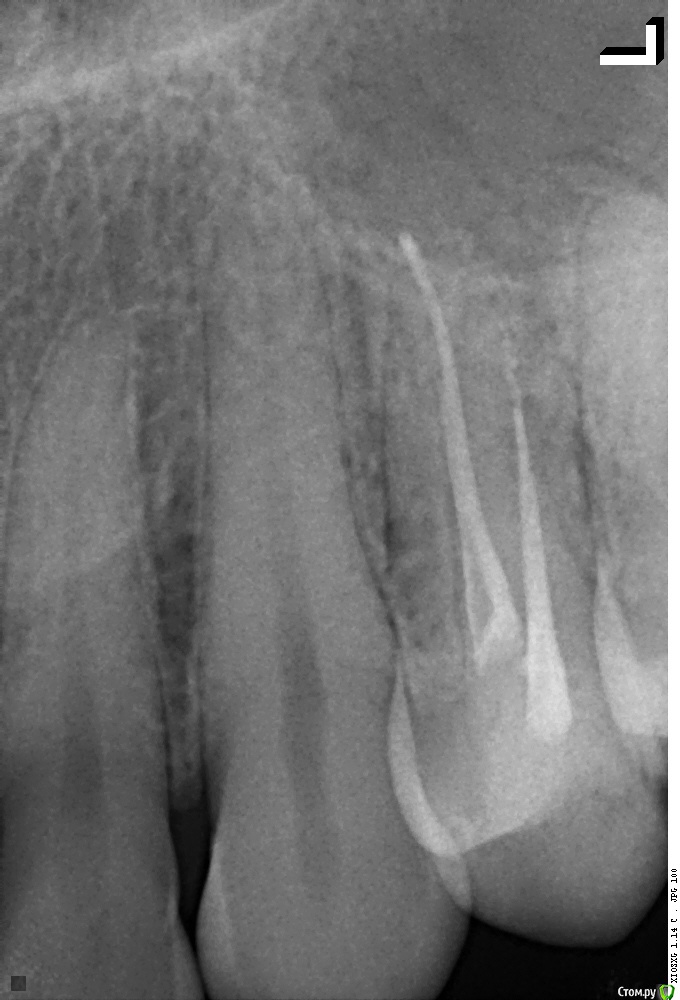

Рентген После и До лечения:

В Вашем зубе 2 канала. По снимку один из них запломбирован хорошо на всю длину, а второй не совсем до конца.  Это может быть причиной боли.

Помимо этого после лечения каналов в принципе возможен дискомфорт при надавливании, должен уменьшаться и за несколько дней пройти совсем.